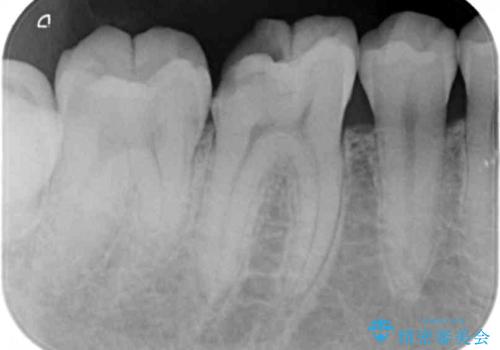

1. 放置してしまった虫歯の治療の治療前